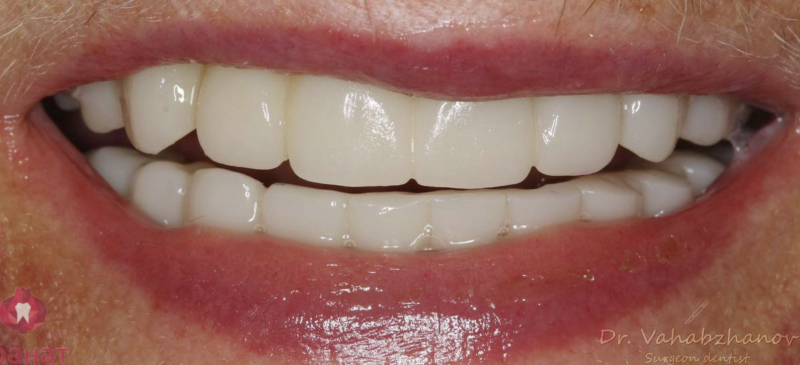

Тотальное протезирование верхней челюсти металлокерамическими коронками с опорой на имплантаты Astra-Tech (Швеция) с левой стороны, и на свои зубы с правой стороны